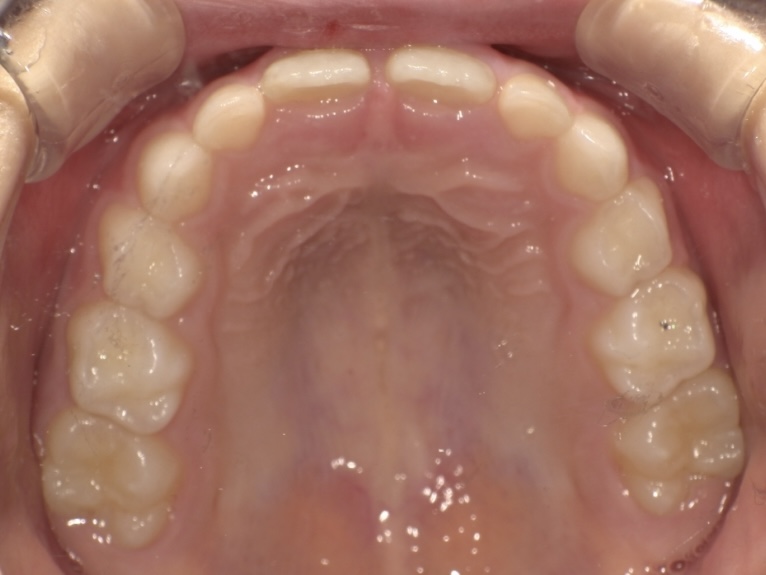

6歳女児 ガタガタと噛み合わせが気になる

下の前歯のガタガタと、深い噛み合わせが気になるとご来院されました。

原因根本から治療するプレオルソを使用、その後成長を利用して歯列を拡大することで歯並びを整えるインビザラインファーストに移行してマウスピース矯正を行いました。

お子様自身も前向きに、積極的に治療に取り組んでくださったので順調に治療が進み、1年半で健康で美しい歯並びになられました。

BEFORE

AFTER

| 年齢・性別 | 6歳女児 |

| 主訴 | 下前歯のガタガタと深い噛み合わせが気になる |

| 施術内容 | プレオルソ+インビザラインファースト |

| 治療期間 | 1年6ヶ月 |

| 費用 | 594,000円(税込) |

| リスク/副作用 | 全ての方で、疼痛、咬合痛、歯根吸収、歯肉退縮、歯髄壊死が生じる可能性があります。 |

| その他注意点 | 指定した時間、マウスピースをつけていただけない場合は治療期間が長くなる場合があります。 |